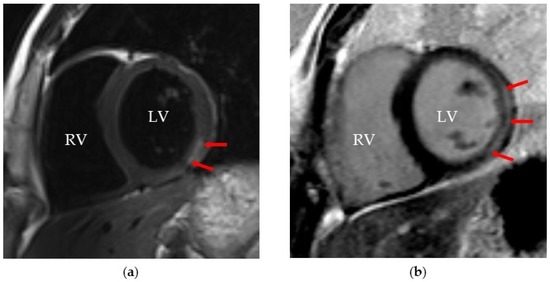

- Lurz, P.; Eitel, I.; Adam, J.; Steiner, J.; Grothoff, M.; Desch, S.; Fuernau, G.; de Waha, S.; Sareban, M.; Luecke, C.; et al. Diagnostic performance of cmr imaging compared with emb in patients with suspected myocarditis. JACC Cardiovasc. Imaging 2012, 5, 513–524. [Google Scholar] [CrossRef] [PubMed]

- Abdel-Aty, H.; Boye, P.; Zagrosek, A.; Wassmuth, R.; Kumar, A.; Messroghli, D.; Bock, P.; Dietz, R.; Friedrich, M.G.; Schulz-Menger, J. Diagnostic performance of cardiovascular magnetic resonance in patients with suspected acute myocarditis: Comparison of different approaches. J. Am. Coll. Cardiol. 2005, 45, 1815–1822. [Google Scholar] [CrossRef] [PubMed]

- Fenster, B.E.; Chan, F.P.; Valentine, H.A.; Yang, E.; McConnell, M.V.; Berry, G.J.; Yang, P.C. Images in cardiovascular medicine. Cardiac magnetic resonance imaging for myocarditis: Effective use in medical decision making. Circulation 2006, 113, e842–e843. [Google Scholar] [CrossRef] [PubMed]

- Etesami, M.; Gilkeson, R.C.; Rajiah, P. Utility of late gadolinium enhancement in pediatric cardiac mri. Pediatr. Radiol. 2016, 46, 1096–1113. [Google Scholar] [CrossRef] [PubMed]

- Friedrich, M.G.; Sechtem, U.; Schulz-Menger, J.; Holmvang, G.; Alakija, P.; Cooper, L.T.; White, J.A.; Abdel-Aty, H.; Gutberlet, M.; Prasad, S.; et al. Cardiovascular magnetic resonance in myocarditis: A jacc white paper. J. Am. Coll. Cardiol. 2009, 53, 1475–1487. [Google Scholar] [CrossRef] [PubMed]

- Mahrholdt, H.; Goedecke, C.; Wagner, A.; Meinhardt, G.; Athanasiadis, A.; Vogelsberg, H.; Fritz, P.; Klingel, K.; Kandolf, R.; Sechtem, U. Cardiovascular magnetic resonance assessment of human myocarditis: A comparison to histology and molecular pathology. Circulation 2004, 109, 1250–1258. [Google Scholar] [CrossRef] [PubMed]

- Luetkens, J.A.; Homsi, R.; Sprinkart, A.M.; Doerner, J.; Dabir, D.; Kuetting, D.L.; Block, W.; Andrie, R.; Stehning, C.; Fimmers, R.; et al. Incremental value of quantitative cmr including parametric mapping for the diagnosis of acute myocarditis. Eur. Heart J. Cardiovasc. Imaging 2016, 17, 154–161. [Google Scholar] [CrossRef] [PubMed]

- Lurz, P.; Luecke, C.; Eitel, I.; Fohrenbach, F.; Frank, C.; Grothoff, M.; de Waha, S.; Rommel, K.P.; Lurz, J.A.; Klingel, K.; et al. Comprehensive cardiac magnetic resonance imaging in patients with suspected myocarditis: The myoracer-trial. J. Am. Coll. Cardiol. 2016, 67, 1800–1811. [Google Scholar] [CrossRef] [PubMed]

- Goitein, O.; Matetzky, S.; Beinart, R.; di Segni, E.; Hod, H.; Bentancur, A.; Konen, E. Acute myocarditis: Noninvasive evaluation with cardiac mri and transthoracic echocardiography. AJR Am. J. Roentgenol. 2009, 192, 254–258. [Google Scholar] [CrossRef] [PubMed]